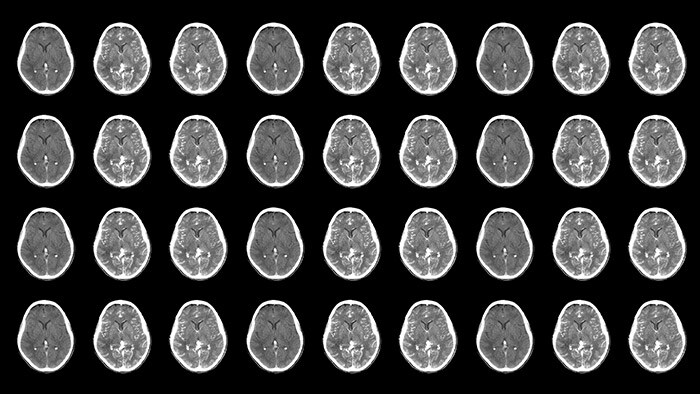

Neurovascular decisions are based on what you see, so see more

Neurovascular care encompasses a remarkable range in approaches to treatment. On one hand, stroke cases are acute and always require immediate treatment for the greatest chance of improving the patient’s quality of life. On the other hand, planned procedures such as complex treatments for aneurysms and arteriovenous malformations (AVMs) need to be meticulously designed and executed to minimize the inherent risk. Neuro suite with SmartCT makes advanced 3D imaging accessible, offering superior workflow with excellent image quality at low dose. Innovative stroke tools, thoughtful collaboration with partners and 24/7 support help you deliver superior neurovascular care.

Neuro suite offers a flexible portfolio of sophisticated 3D imaging, integrated imaging, integrated technologies, neuro accessories and valued-added services that puts you on top of things, whether treating an acute stroke patient or working precisely through a complex AVM. This allows you to act with confidence, supported by high levels of procedural efficiency and standardization to help redefine outcomes for your patients and provide a positive workflow experience for staff.